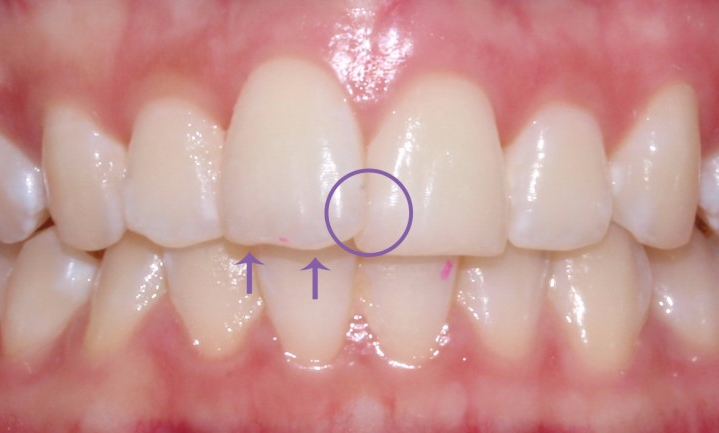

환자분의 상태는

상악 중절치와

앞니 절단연의 울퉁불퉁거림이

있는 편이어서

그 부분을 중점으로 치료하며

전체적인 배열에 맞게

2D교정 장치로

진행하기로 하였습니다.

동그라미가 되어있는 부분이

상악 우측 중절치로

치아가 입술 쪽으로 튀어나와

있는 상태입니다.

왼쪽 중절치와 겹쳐 보이고 있습니다.

2D치과는 화살표 부분의

절단연 (씹는면) 은

환자분의 요청에 따라

평평하게 연마하여

진행되었습니다.